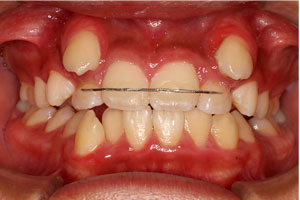

こちらの初診(男性)の患者さんは、開咬合 / 叢生歯列の症状がありました。

1期治療 8歳9ヶ月 2期治療 12歳4ヶ月から治療を開始し、1期治療 7ヶ月 2期治療 2年5ヶ月の間、スタンダードエッジワイズ法(与五沢エッジワイズシステム)を用い矯正治療を行いました。

| 症例分類 | 開咬合 / 叢生歯列 / 偏位咬合 | |||||||||||||||||||||||||||||||||||||||||||||||||||||||||||

| 動的治療期間 | 1期治療 7ヶ月 2期治療 2年5ヶ月 | |||||||||||||||||||||||||||||||||||||||||||||||||||||||||||

| 12歳4ヶ月 | 15歳8ヶ月 | |